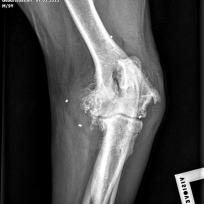

Die Orthopädie beschäftigt sich mit der Entstehung, Verhütung und Behandlung von angeborenen oder erworbenen Problemen des Bewegungsapparates. Die meist daraus resultierenden Lahmheiten werden bei uns umfassend abgeklärt. Hierbei kommen neben einer ausführlichen klinischen Lahmheitsuntersuchung auch weiterführende diagnostische Verfahren, wie Röntgen Computertomografie und Ultraschall zum Einsatz.